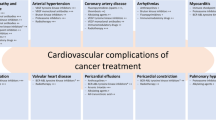

As cancer-related mortality declines steadily due to advances in early cancer detection and anticancer treatment, the importance of anticancer treatment side effects has increased [1,2,3]. Most importantly, among the various adverse consequences of anticancer therapy, cardiovascular toxicity including arrhythmia, thromboembolic events, atrial fibrillation, and cardiac dysfunction has been recognized [4,5,6]. In this context, cardio-oncology has been introduced as a subspecialty that involves a team of cancer surgeons, oncologists, hematologists, radiologists, specialist nurses, pharmacists, and cardiologists [7, 8]. The cardio-oncology team offers prevention, monitoring, and treatment for cardiac complications associated with anticancer treatment [9]. Recently, the European Society of Cardiology (ESC) in collaboration with the European Hematology Association (EHA), the European Society for Therapeutic Radiology and Oncology (ESTRO), and the International Cardio-Oncology Society (ICOS) published the first guidelines on cardio-oncology, and the role of the cardio-oncology team has been systematically established [10]. These guidelines have also standardized definitions of chemotherapy-related cardiovascular toxicity, introducing the term "cancer therapy-related cardiovascular toxicity" (CTR-CVT), which includes various specific conditions, such as cancer therapy-related cardiac dysfunction (CTRCD), immune checkpoint inhibitor (ICI) myocarditis, vascular toxicity, arterial hypertension, and cardiac arrhythmia.

Within CTR-CVT, CTRCD is the most prevalent clinical manifestation [11]. The evidence regarding CTRCD continues to increase, especially in light of the evolution of anticancer therapies, such as HER2-positive targeted drugs, proteasome inhibitors, ICIs, and vascular endothelial growth factor (VEGF) inhibitors [12,13,14,15,16]. At the same time, imaging modalities to diagnose and prognosticate CTRCD are evolving including myocardial strain, myocardial work in transthoracic echocardiography (TTE), cardiac computed tomography (CT), and cardiac magnetic resonance[17,18,19,20,21]. The present review of current data and professional guidelines proposes potential strategies for predicting, monitoring, and tracking CTRCD throughout the cancer treatment process using newly developed anticancer treatments and imaging tests.